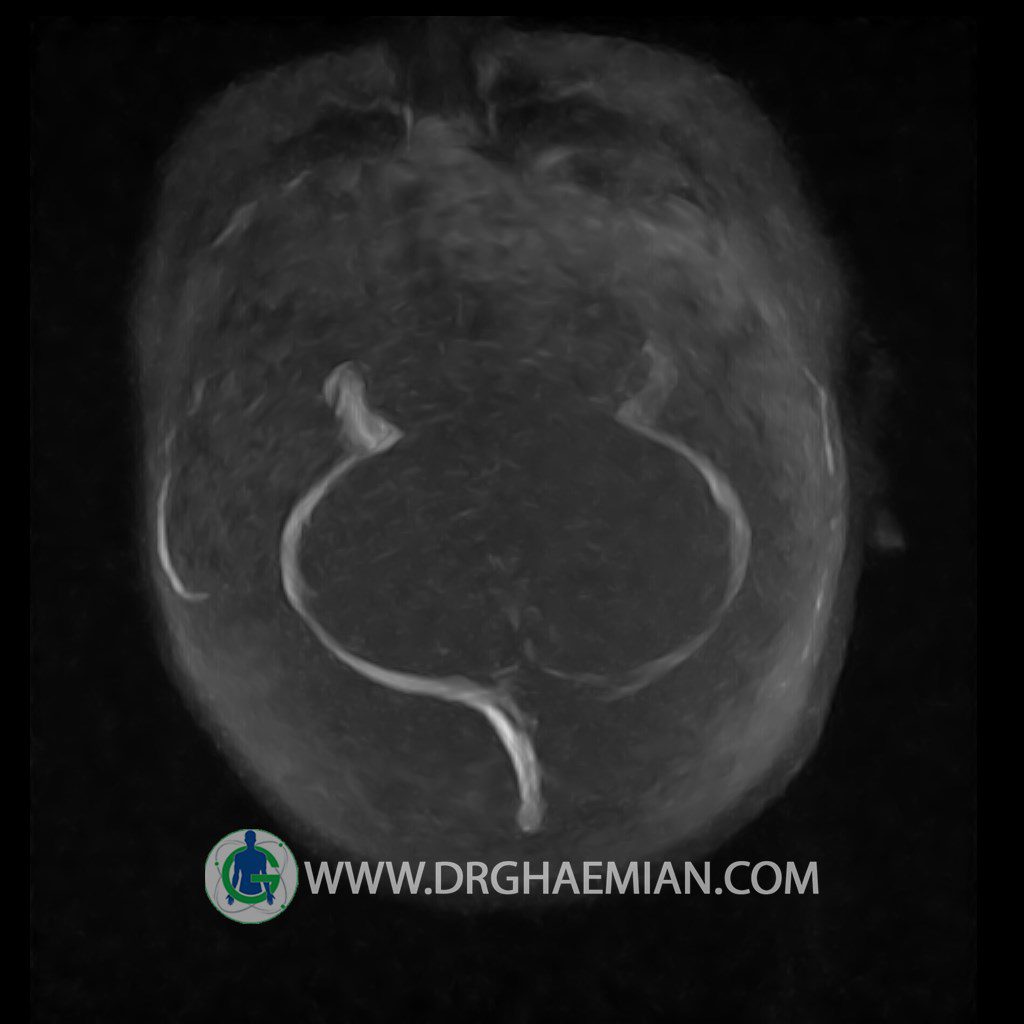

CRANIAL MRV

Technique: TOF ( time of flight ).

Images of the venous cranial vessels demonstrates a superior sagittal sinus of normal caliber with normal arrangement of draining superficial cerebral veins.

The great cerebral vein Galen inferior sagittal , straight sinus and left sigmoid sinuses appear normal.

The right transverse and sigmoid sinuses present a normal caliber.

The other evaluable deep cerebral veins , basal and labbe are normally developed and patent.

– Narrowing of left transverse sinus without inthimal irregularity & without filling defect suggestive for cengenital hypoplasia

– Two high signal focus ( 9 mm & 11 mm in diameter ) in left internal capsule suggestive for ischemic foci & low grade glioma

are seen

COMMENT : brain MRI with contrast is recommended .